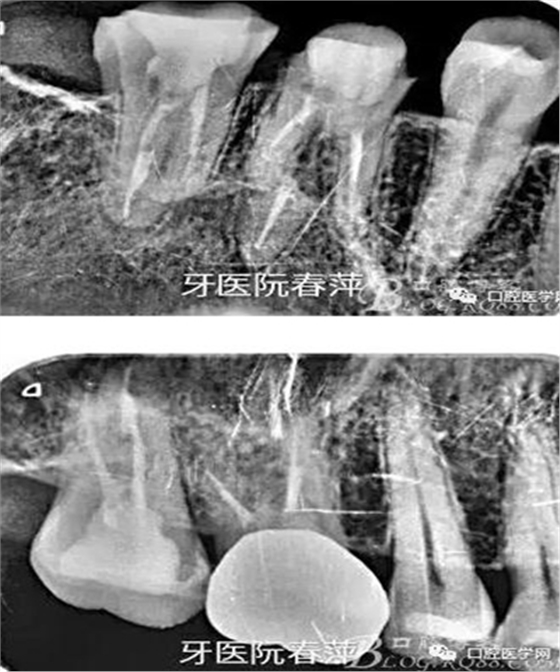

27的治療過程不太順利,主要是干髓近10年,根管很難疏通。腭根最先預(yù)備,比較粗大。近頰根不通暢,選中頰根找不到。

絢彩AT無飾瓷全形態(tài)氧化鋯產(chǎn)品體驗(yàn)+全冠和嵌體微創(chuàng)修復(fù)后牙

因?yàn)槿狈︼@微鏡的幫助,27的根管預(yù)備花了很長時(shí)間,最后終于找到3個(gè)根管也基本疏通到位。完善的根管治療是修復(fù)的根本,這個(gè)是什么時(shí)候都不能改變的基礎(chǔ)觀念。